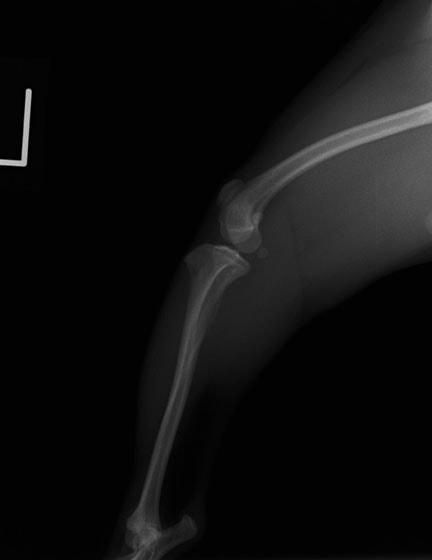

■ 症例22 ポメラニアン 1歳5か月 去勢雄

左後肢の挙上を主訴に来院した。整形学的検査、レントゲン検査より左右の膝蓋骨脱臼(左GradeⅡ〜Ⅲ、右Grade Ⅱ)を認めた。また、脛骨の前方引き出し試験の際に、引き出し兆候は認められないものの、疼痛が認められたため、前十字靭帯の損傷が疑われた。術中における、目視および関節内の操作によって、前十字靭帯の損傷や過伸展といった異常が認められなかったため、膝蓋骨脱臼の整復のみ実施した。手術手技は縫工筋及び内側広筋の解放、脛骨粗面の外側転位、滑車ブロック形造溝術、内外側関節包の縫縮を実施した。本症例は跛行もなく経過良好である。しかし、頸骨高平部の角度(TPA)が 右26.2°、左24.9°であり、解剖学的に前十字靭帯損傷のリスクが高いことから今後の経過に注意が必要である。